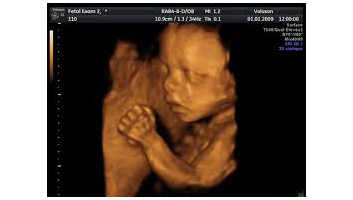

- Echographie doppler de la femme enceinte en 4D